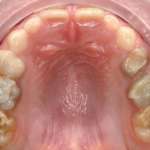

Riabilitazione adesiva minimamente invasiva di arcate con estesa usura dentale Premium

Viene presentata una metodica per la ricostruzione diretta di elementi con severa usura dentale che permette, nella fase preliminare, di verificare l’accettabilità da parte del paziente delle modifiche occlusali che verranno apportate. Viene riportata l’analisi retrospettiva di 20 casi con un follow-up di sei anni